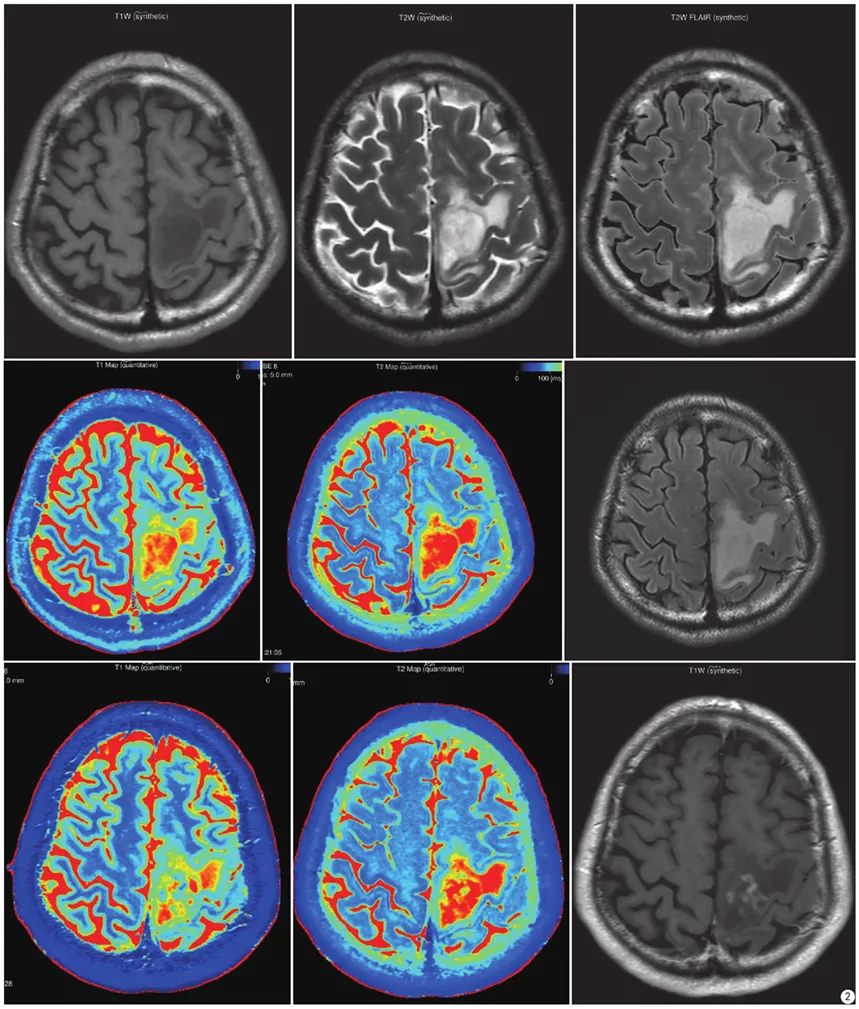

高级别胶质瘤。从左至右、从上到下分别是:合成图像(T1WI、T2WI、T2 FLAIR);合成T1 mapping、合成T2 mapping、常规扫描T2 FLAIR;增强后合成图像(T1 mapping+C、T2 mapping+C、T1WI+C)

低级别胶质瘤。从左至右、从上到下分别是:合成图像(T1WI、T2WI、T2FLAIR);合成T1 mapping、合成T2 mapping、常规扫描T2 FLAIR;增强后合成图像(T1 mapping+C、T2 mapping+C、T1WI+C)